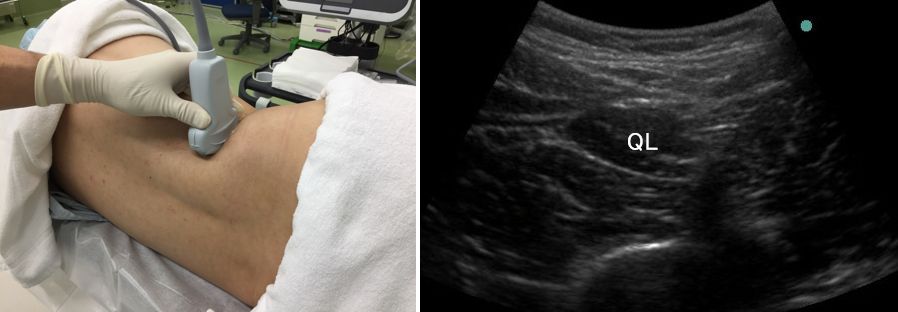

(1)まずは、L4付近でシャムロックビューを出しましょう。

これはテキスト第2版165項と同じものですね。

(2)腰方形筋が同定できたら、プローブを頭側へ移動し

腰方形筋の形が変化していく様子を観察します。

扁平になりましたね。